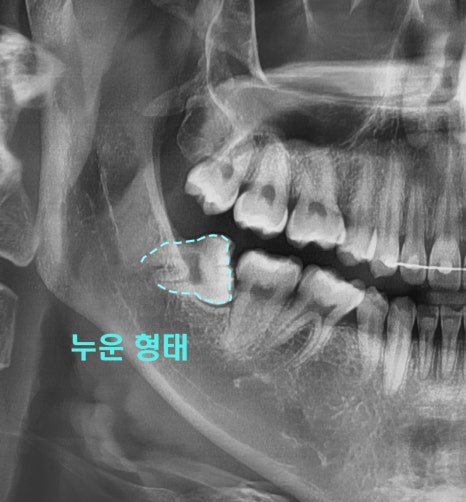

안녕하십니까, 더서울 문정동치과 쌍둥이 박현성 원장입니다. 사랑니라는 치아가 생겼을때, 의료진들은 되도록 빠른 시일 내에 빼는 것이 좋다 그렇게 알려드리고